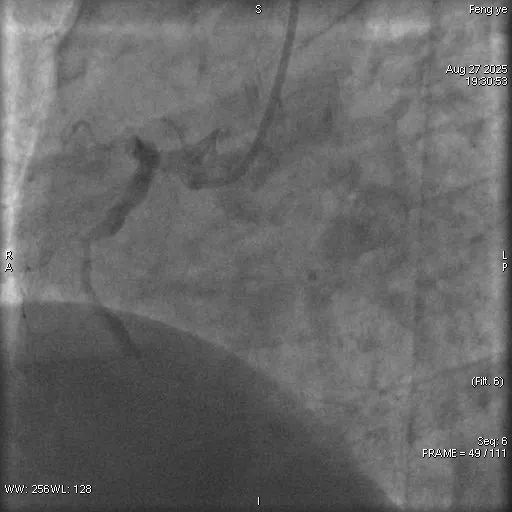

术前

术后

紧急救治:介入手术打通血管,从死亡线拉回生命

抵达四院急诊室时,张先生的病情已十分危急。医护人员早已备好除颤仪以防万一,同时迅速为其完善心电图、心肌酶谱等关键检查。检查结果显示,张先生患上的是急性下壁正后壁心肌梗死—— 这是一种发病急、致死率高的心血管急症,若不及时干预,随时可能致命。

接到紧急会诊通知的四院心内科主任刘永生,第一时间赶到急诊室。结合张先生 “长期吸烟、高血压、高血糖、肥胖” 的病史与检查结果,刘永生判断其冠状动脉已出现急性闭塞,必须立即通过介入手术开通血管,否则将错失抢救时机。

随后,张先生被快速转运至导管室。刘永生带领团队精准定位其心脏冠状动脉闭塞部位,成功植入支架,打通了堵塞的血管。经过紧张抢救,张先生的生命体征逐渐平稳,胸闷、胸痛等症状明显缓解,最终脱离生命危险。目前,他已康复出院,出院后不仅彻底戒掉了多年烟瘾,还主动制定健康饮食与减重计划,积极配合后续康复治疗。